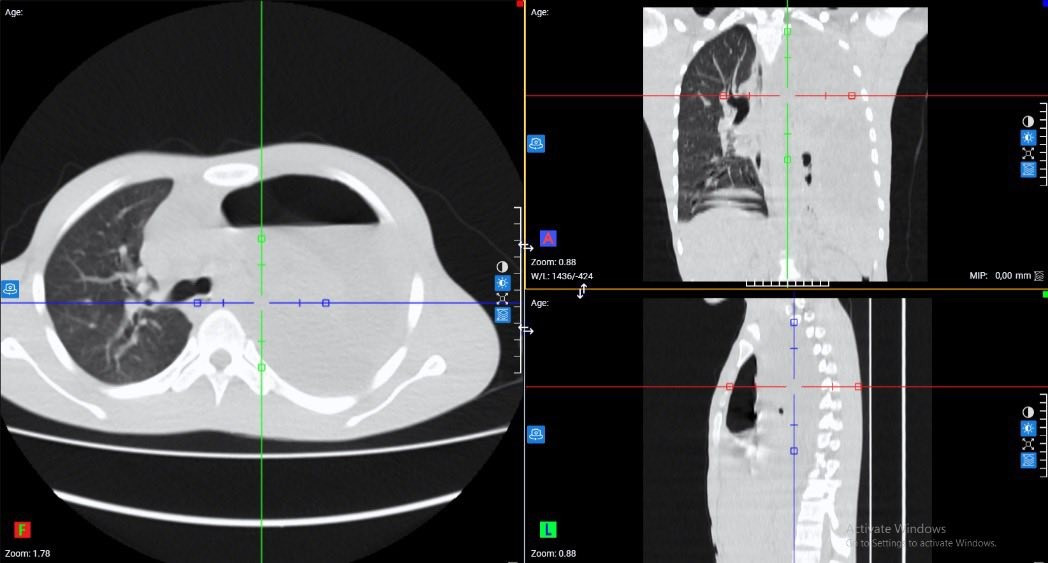

Bệnh nhân nam (20 tuổi) nhập viện trong tình trạng đau ngực trái kèm khó thở đã kéo dài 1 tuần. Qua thăm khám lâm sàng, bệnh nhân có biểu hiện vẻ mặt nhiễm trùng , SpO2 94%, mạch nhanh 130 lần/phút, huyết áp thấp 90/60 mmHg.

Hình ảnh phổi tổn thương trên phim chụp - Ảnh BVCC

Kết quả xét nghiệm máu cho thấy tình trạng nhiễm trùng nặng với chỉ số bạch cầu (WBC) lên tới 64.8 G/L, chỉ số CRP cao 263.6 mg/dL. Với hệ thống chẩn đoán hình ảnh hiện đại, các bác sĩ ghi nhận: Đông đặc nhu mô thùy dưới phổi trái, tràn dịch màng phổi trái lượng nhiều, tràn khí màng phổi trái, phổi trái bị xẹp thụ động, đẩy lệch trung thất sang phải.

Các bác sĩ khoa Ngoại Tổng hợp đã nhanh chóng đưa ra chẩn đoán: "Viêm phổi màng phổi trái biến chứng tràn mủ màng phổi" và chỉ định can thiệp ngoại khoa cấp cứu.